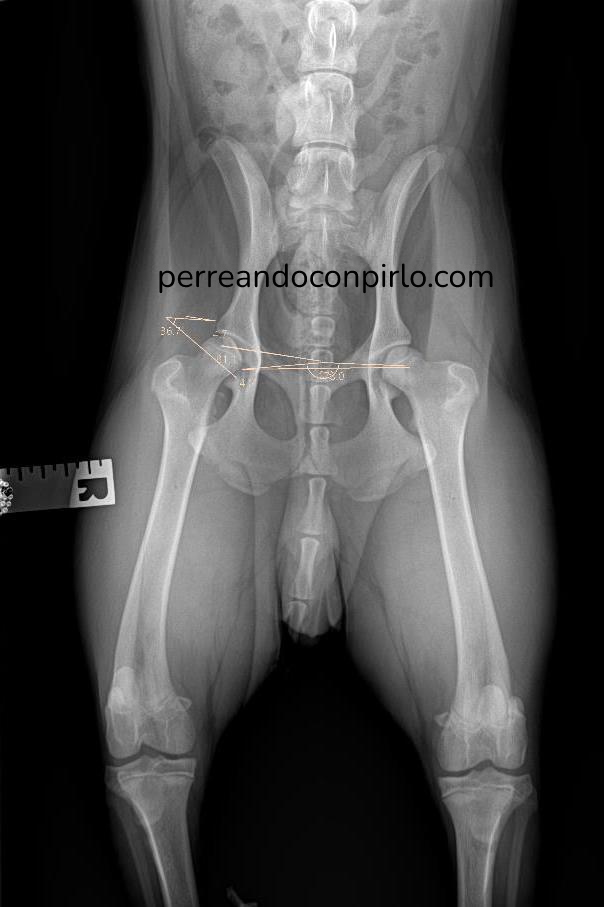

Hacer radiografía sin sedación a un perro para detectar o descartar displasia, puede servir como primera prueba pero poco más. Los resultados que arroje van a ser poco específicos, dado que para poder posicionar al perro en la postura adecuada se le tiene que poner en una postura antinatural y por lo tanto se le causa dolor: por tanto, si el perro no está dormido, no dejará que lo posiciones como corresponde y la imagen que se realice será aproximada.

Por eso es tan importante hacer un estudio radiológico con sedación para detectar la gravedad de una displasia de cadera.

Así que esto fue lo que vimos en una de las 4 radiografías realizadas. En el lado izquierdo está la radiografía buena (con el perro sedado), y en el lado derecho ponemos al lado la radiografía previa sin sedación para que veas cómo cambia el diagnóstico cuando el perro está en la posición correcta:

El diagnóstico es bastante más feo. Pirlo tiene displasia grave de cadera. La cabeza del fémur apenas entra en el acetábulo unos milímetros, en el caso de la pata derecha. Esto quiere decir que al caminar, la cabeza del fémur posiblemente se salga por completo de la cavidad y cuando eso sucede, el perro cojea. Al parar, se recoloca la pata y deja de cojear hasta que vuelve a suceder lo mismo tras unos minutos caminando.